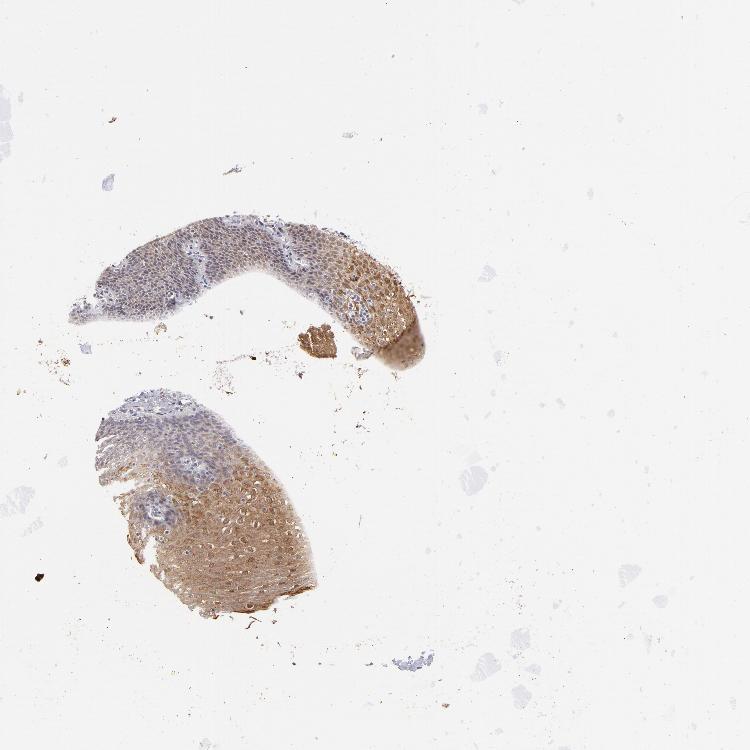

ESOPHAGUS - Antibody stainingi

Antibody staining in the annotated cell types in the current human tissue is reported as not detected, low, medium, or high, based on conventional immunohistochemistry profiling in selected tissues. This score is based on the combination of the staining intensity and fraction of stained cells.

Each image is clickable and will lead to virtual microscopy that enables deeper exploration of all samples and also displays staining intensity scores, fraction scores and subcellular localization as well as patient and tissue information for each sample.

Antibody CAB002615

Squamous epithelial cells Medium